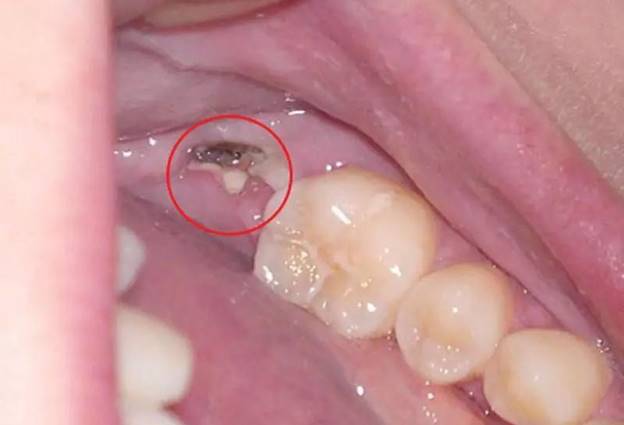

Trước khi biết còn chân răng có nên nhổ không thì cần biết dấu hiệu nhận biết còn sót chân răng trong hàm. Sau khi nhổ răng, việc cảm thấy đau nhức là phản ứng bình thường của cơ thể. Tuy nhiên, một số lúc cơn đau kéo dài hơn 2 – 3 ngày mà không thuyên giảm. Thậm chí có xu hướng nặng hơn kèm theo sưng tấy, viêm nhiễm. Lúc này rất có thể nguyên nhân là do chân răng còn sót lại trong ổ nhổ. Trong trường hợp này, người bệnh cần đến ngay cơ sở nha khoa. Thông qua đó bác sĩ kiểm tra, xác định chính xác tình trạng và có phương án xử lý kịp thời.

- Cơn đau không giảm sau 2 – 3 ngày, thậm chí có xu hướng tăng lên.

- Vùng nướu quanh ổ nhổ có thể bị sưng đỏ, đau nhức và có dấu hiệu nhiễm trùng.

- Sờ vào vùng nhổ răng và cảm thấy có một cục cứng nhỏ. Điều đó có thể là phần chân răng còn sót lại.

- Máu vẫn rỉ ra nhiều ngày sau nhổ hoặc xuất hiện mùi hôi khó chịu. Có thể ổ nhổ đã bị viêm nhiễm do phần chân răng chưa được lấy hết.